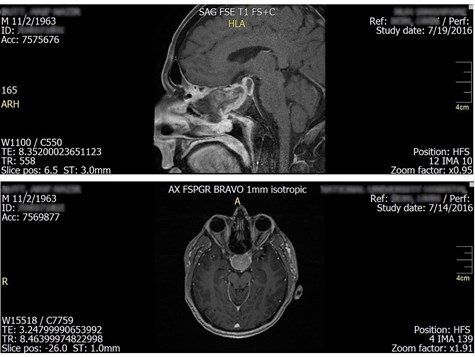

Figure 1: Gadolinium-enhanced MRI (T1-weighted sagittal and axial views) showing a 2.9 × 2.8 × 2.8 cm homogeneously enhancing pituitary macroadenoma compressing the optic chiasm.

Magnetic resonance imaging of the brain and orbit revealed a pituitary macroadenoma compressing the optic chiasm. The lesion did not clearly extend to involve the optic tract, but its mass effect was sufficient to explain the homonymous-like field loss, likely due to asymmetric or lateralised chiasmal compression.